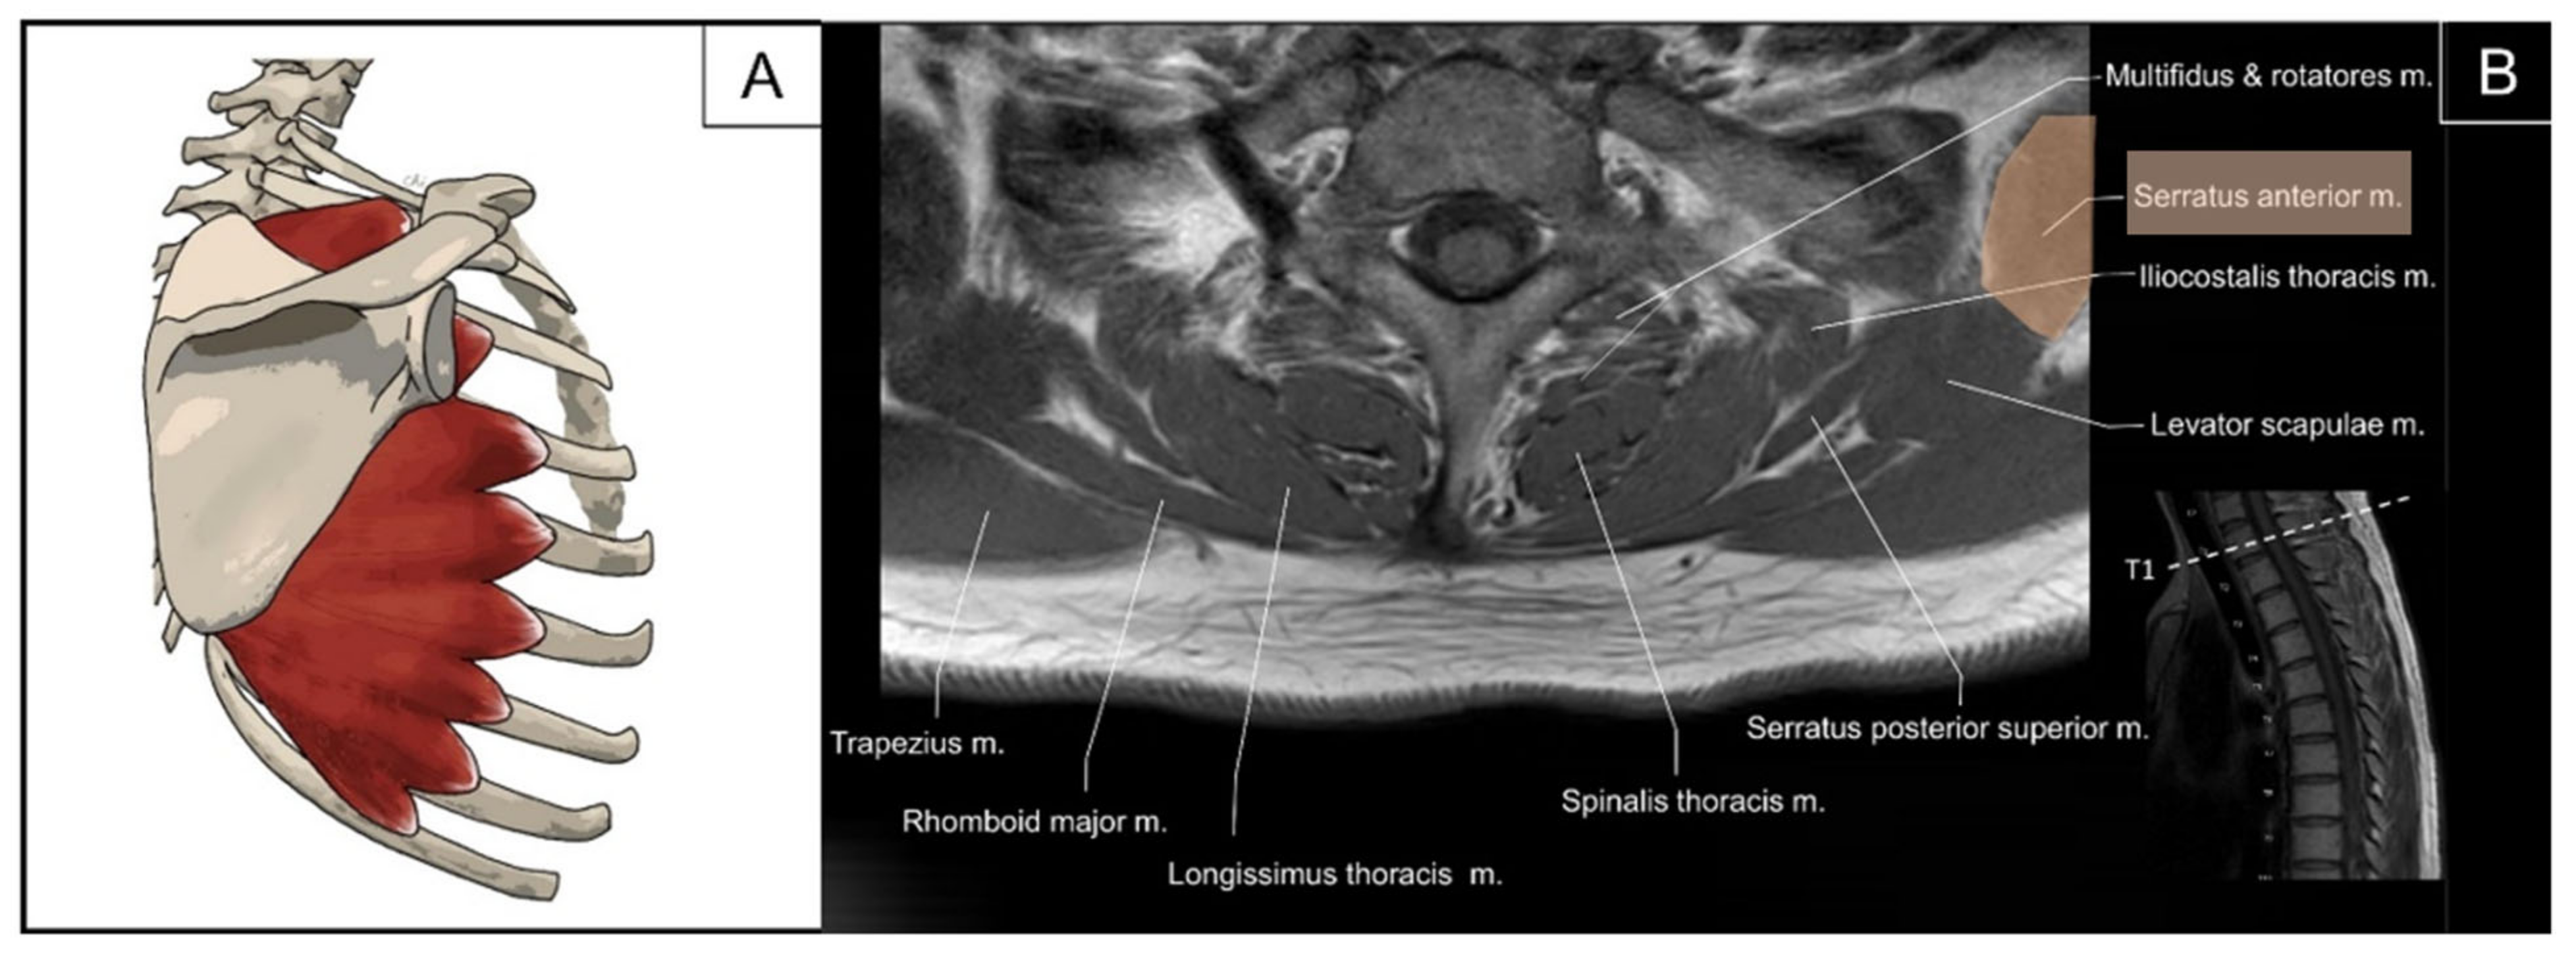

5.1. Iliocostalis Thoracis, Longissimus Thoracis, Semispinalis Thoracis, and Thoracic Multifidus

5.1.1. Anatomy

5.1.2. Sonographic Scanning

5.1.3. Clinical Relevance